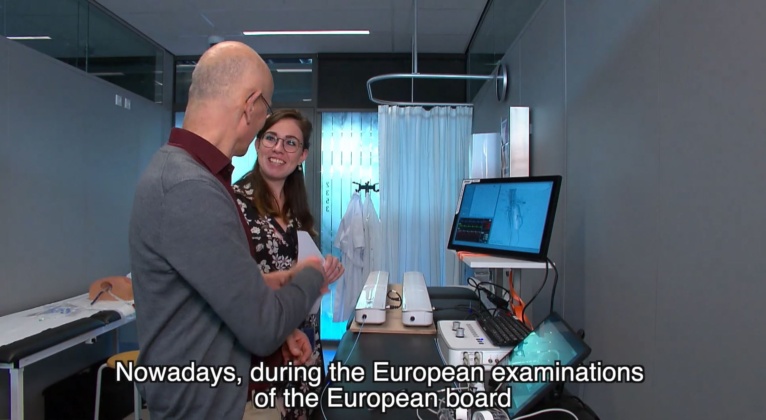

How To Improve a Physician’s Competency

See how ANGIO Mentor plays a prominent role in Dutch vascular surgeons certification.

“One of the outcomes of this nationwide course we are doing for 9 years is that the level of (endo)vascular knowledge and skills (competencies) in all regions in the Netherlands is clearly improved…

Prof. Bob Geelkerken

Consultant vascular surgeon, University of Twente, former chair of Dutch Society of Vascular Surgery